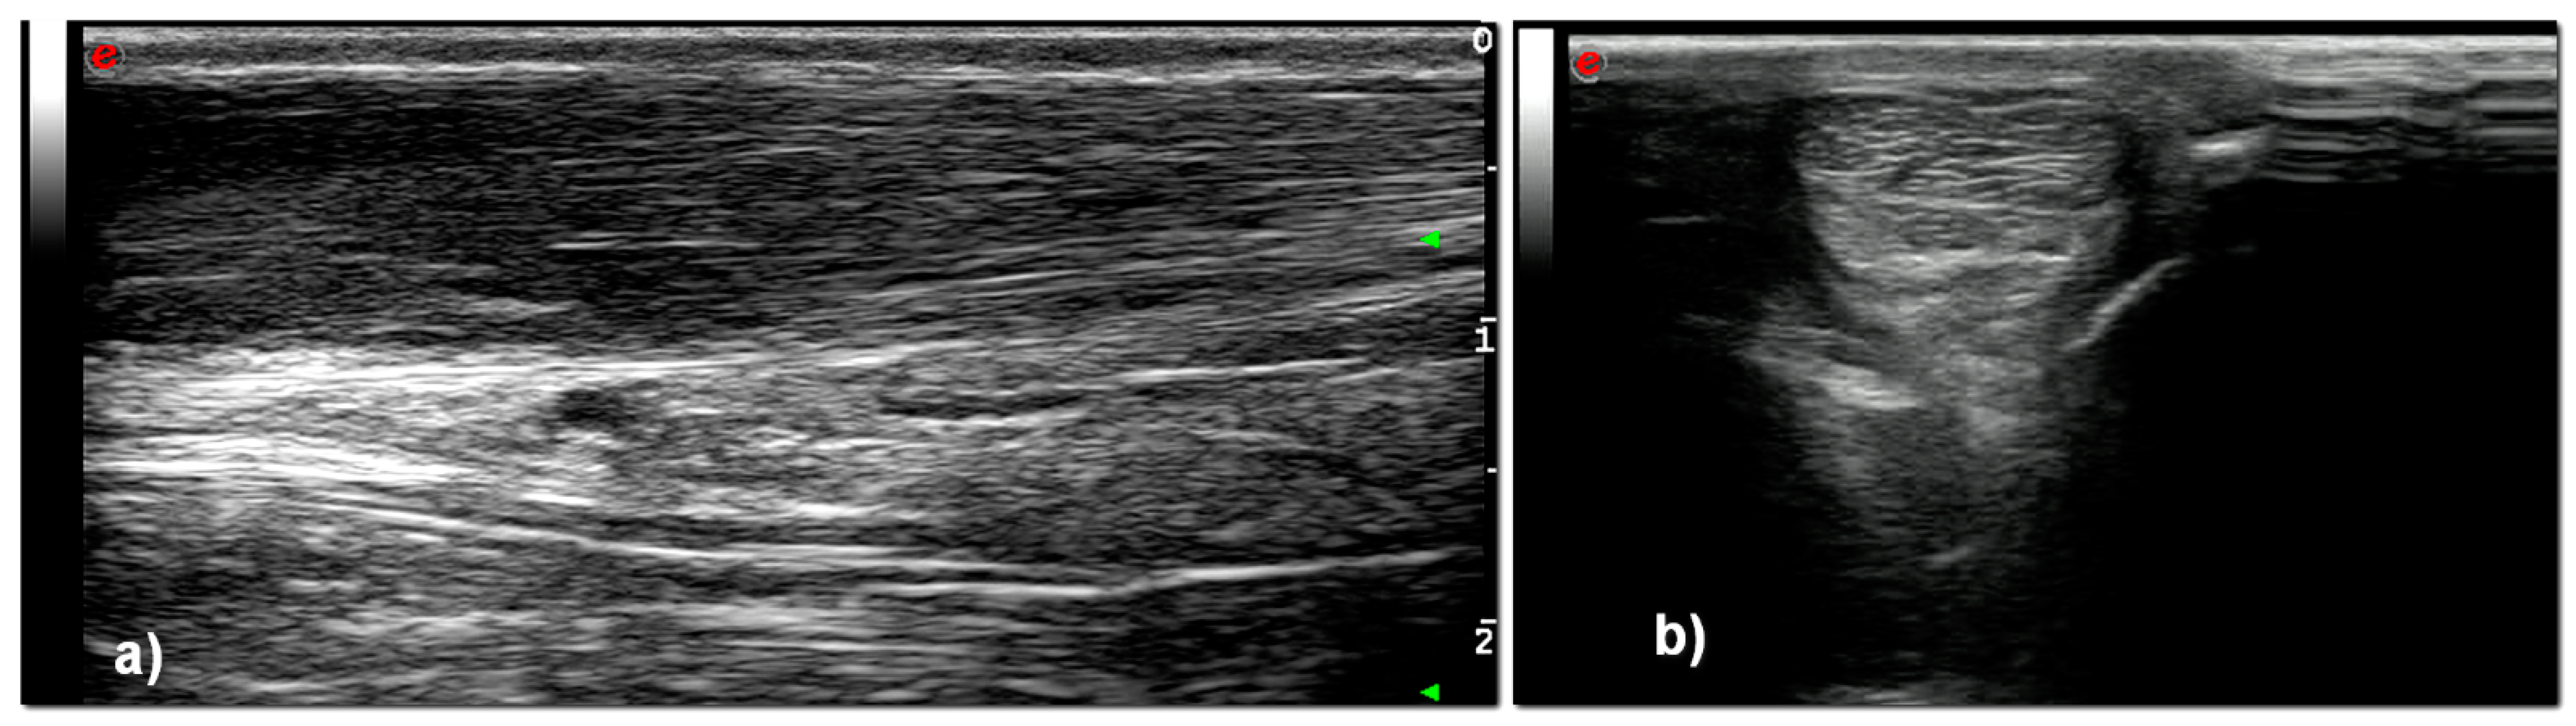

3. Results